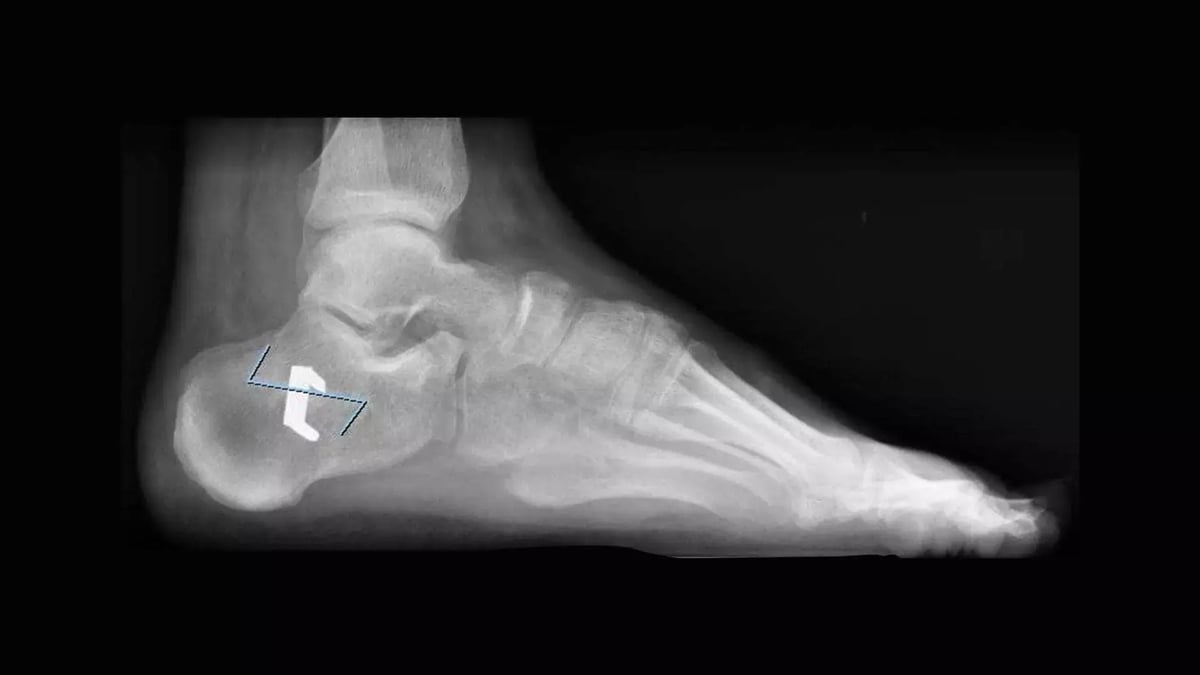

Indubbiamente l’esame a noi più utile è un esame di primo livello: una radiografia del piede e talvolta anche della caviglia in carico.

Talvolta in alcuni planning chirurgici, possono risultare necessarie particolari proiezioni,. Personalmente ritengo utile ed spesso indispensabile richiedere una proiezione radiografica, ideata dal collega Charles L. Saltzman, che si esegue in carico, da posteriore con inclinazione del raggio a 20 gradi.

Si tratta di una proiezione che permette di mettere in relazione retropiede e caviglia, molto importante nel valutare le deformità e capire quale sia la correzione più efficace formulando il corretto planning chirurgico.